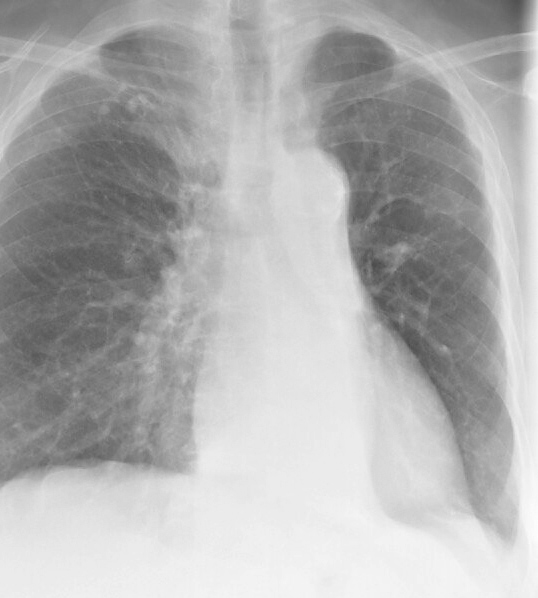

LLL Collapse Case 7 PA